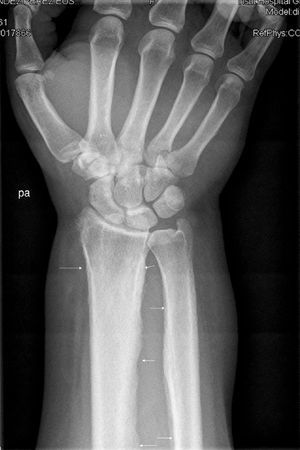

The patient, a 45-year-old male, was referred to the rheumatology clinic due to diffuse joint pain on the wrists and knees. The patient was diagnosed with liver cirrhosis and severe hepatopulmonary syndrome. Physical examination showed swelling of the knees and wrists (arthritis) and clubbing. The X-rays requested showed periosteal thickening observed continuously, in a diaphysometaphysiary location of the radius and ulna in both forearms, and predominantly in distal femurs and both knees, compatible with nonaggressive periosteal reaction. Fig. 1 shows periosteal thickening affecting both femurs on the concave bone edge and respecting the epiphysis, and equal involvement of the radius and ulna on the right wrist, in Fig. 2.

The findings on physical examination were finger-clubbing and arthritis of the hands and knees, and the radiological presence of continuous noninvasive periostitis of the concave edge affecting the long bones of both the upper and lower extremities, with a diagnosis of hypertrophic osteoarthropathy. This clinical entity is mainly associated with intrathoracic processes (especially malignancy, namely lung cancer and pleural tumors), but also other diseases among which one can include liver disease (hepatocellular carcinoma, alcoholic hepatitis and both Portal biliary cirrhosis and cirrhosis of the liver).1–3